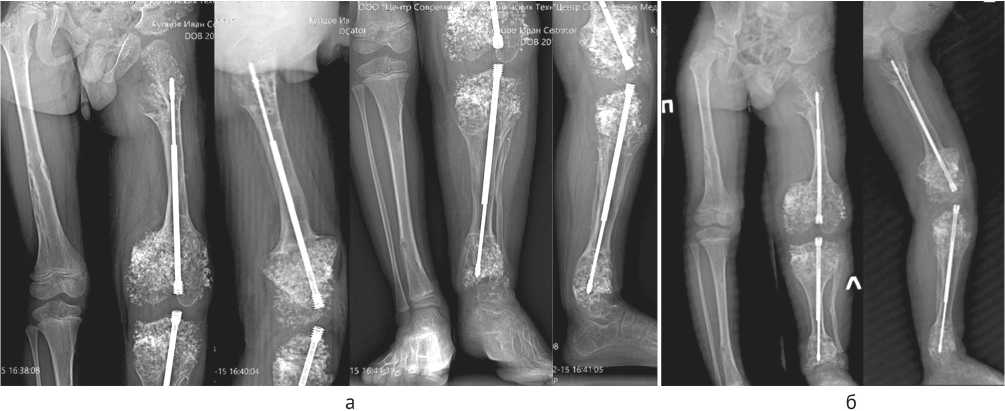

Контрольные осмотры производили через шесть и через 12 месяцев после демонтажа аппарата внешней фиксации. Отмечен продолжающий рост удлиненных сегментов, отсутствие рецидива деформаций и корректное телескопирование титановых телескопических стержней, без блокирования расхождения и без протрузии в коленный или голеностопный суставы. Ремоделирование костной мозоли имело все признаки перестройки здоровой костной ткани без включения хондроматозных очагов в ее структуру (рис. 8).

Рис. 8. Рентгенограммы через шесть месяцев (а) и 12 месяцев (б) после демонтажа аппарата Илизарова

В итоге, количественные параметры лечения составили:

• —    удлинение бедра 5,8 см, удлинение голени 5,6 см, что суммарно составило 24,5 % от исходной длины конечности,

• —    суммарный индекс внешней фиксации составил 12,02 дн/см,

• —    учитывая исход лечения, а также встретившееся осложнение, которое потребовало выполнения незапланированного вмешательства в период до демонтажа аппарата Илизарова, но не повлекшее ухудшения достигнутого результата, исход удлинения можно классифицировать как соответствующий степени IIa по классификации Lascombes [19].